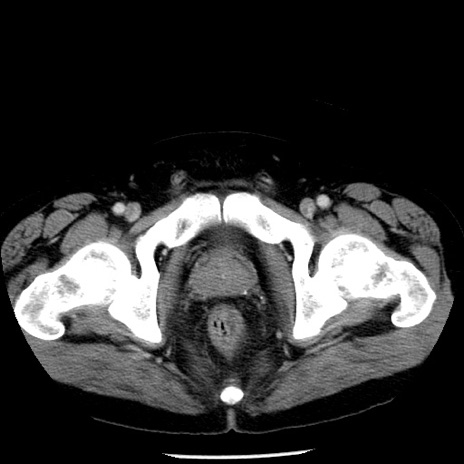

症例29(横断像)

【症例】40歳代男性

【現病歴】2日前から胃痛あり。徐々に周期的な激痛に変化した。本日になっても激痛があるため受診。

【身体所見】意識清明、BT 38-39℃台あり、腹部:膨満、やや硬、右下腹部に圧痛あり。

【データ】WBC 8500、CRP 23.26